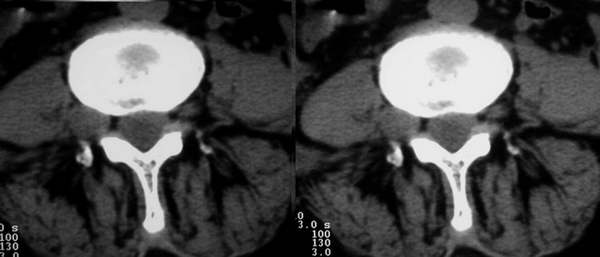

标题: CT3877:神经纤维瘤 [打印本页]

标题: CT3877:神经纤维瘤

女:67岁,右下肢疼痛20余年。

行腰椎间盘扫描。

右侧椎间孔外侧见类圆形软组织肿块边缘清与右神经根关系密切

考虑神经鞘瘤

右侧椎间孔外侧见类圆形软组织肿块边缘清与右神经根关系密切。片子上标明了左和右了吗?正常的ct图像病变应该是在右侧呀!为和这么多人考虑或支持左侧!!!! 考虑右侧神经鞘瘤